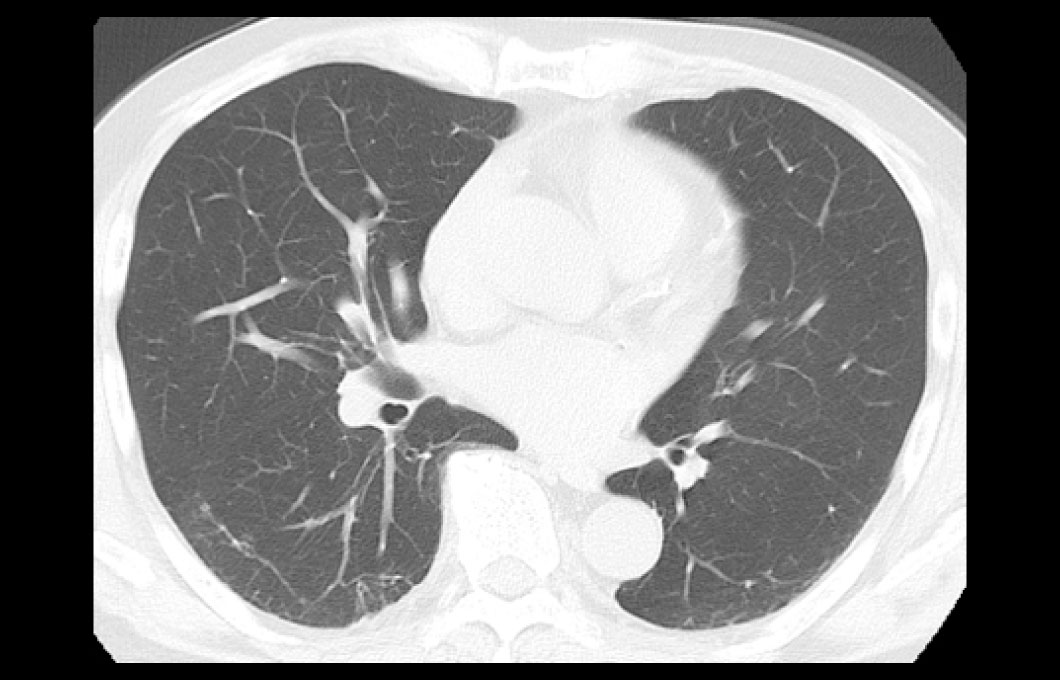

X線とコンピュータを使い人体各部の横断像(輪切り像)を画像にします。脳、肺、肝臓、筋肉等のあらゆる部位・臓器の小さな病変を診断することができます。